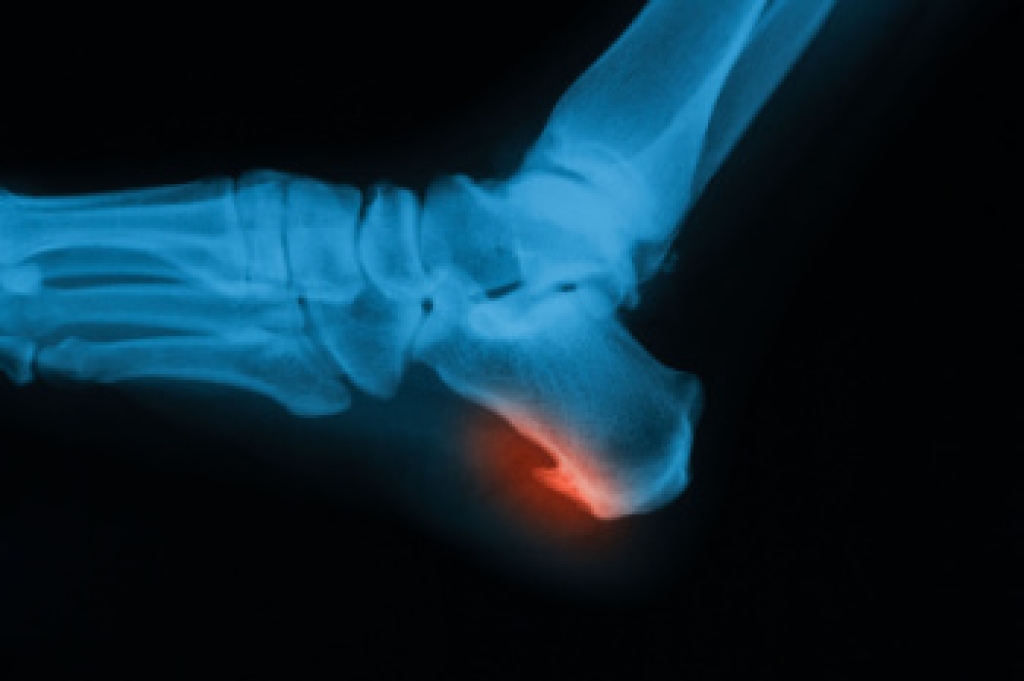

Swollen feet can also be caused by bone and tendon conditions, including fractures, arthritis, and tendinitis. Additionally, there may be skin and toenail conditions and an infection may cause the feet to swell. Patients who take medicine to treat high blood pressure may be prone to getting swollen feet.